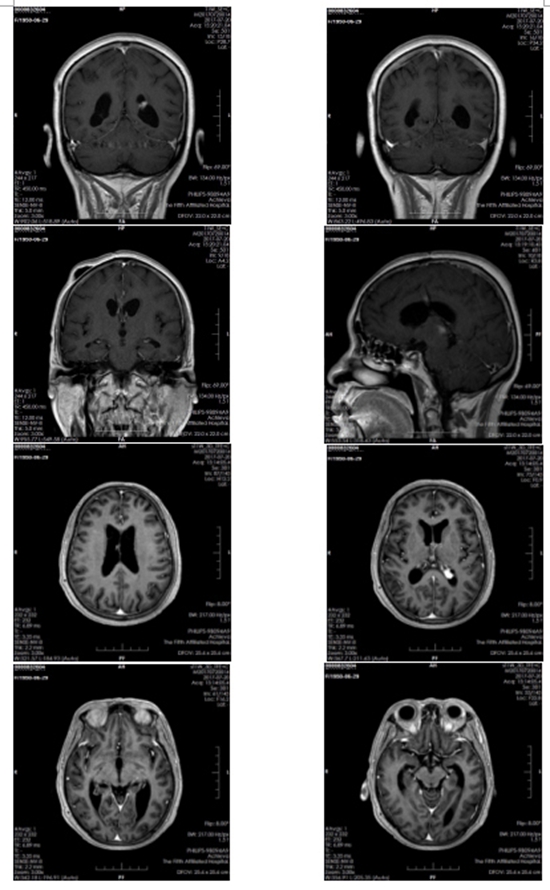

患者放疗前核磁共振图

2017年4月29日,王大妈来到了郑大五附院接受治疗,先是住进了神经外科,神经外科主任医师寿纪新主任介绍说:“当时病人外院核磁共振显示两侧脑室、三脑室、四脑室及松果体内见多发占位,合并梗阻性脑积水、脑室周围脑白质间质性脑水肿及脊髓转移,病情重,病灶广泛,无法手术切除”。为缓解脑积水,给病人进行了“三脑室底造瘘+脑室腹腔分流术”,手术后患者病情稳定、症状改善出院。

然而,好景不长,2017年5月16日,王大妈因突发意识模糊再次来到郑大五附院,复查头部MRI提示颅内肿瘤较前明显增大,且病变波及到脑干,脑脊液循环受阻。经放疗科主任医师王晓瑜主任会诊考虑颅内多发占位,恶性淋巴瘤可能性大,不排除生殖细胞瘤。当时病人神志模糊,下肢肌力0级,大小便失禁,病情危重,随时有呼吸、心跳骤停的风险。但肿瘤细胞对放射线敏感,经积极地放射治疗有可能挽救病人生命。但放疗风险大,可加重脑水肿。经与患者家属反复沟通,最终家属接受了放射治疗。然而,通过放疗究竟能否成功挽回王大妈的生命,这仍然是个未知数,也是所有人在面临的极大考验。